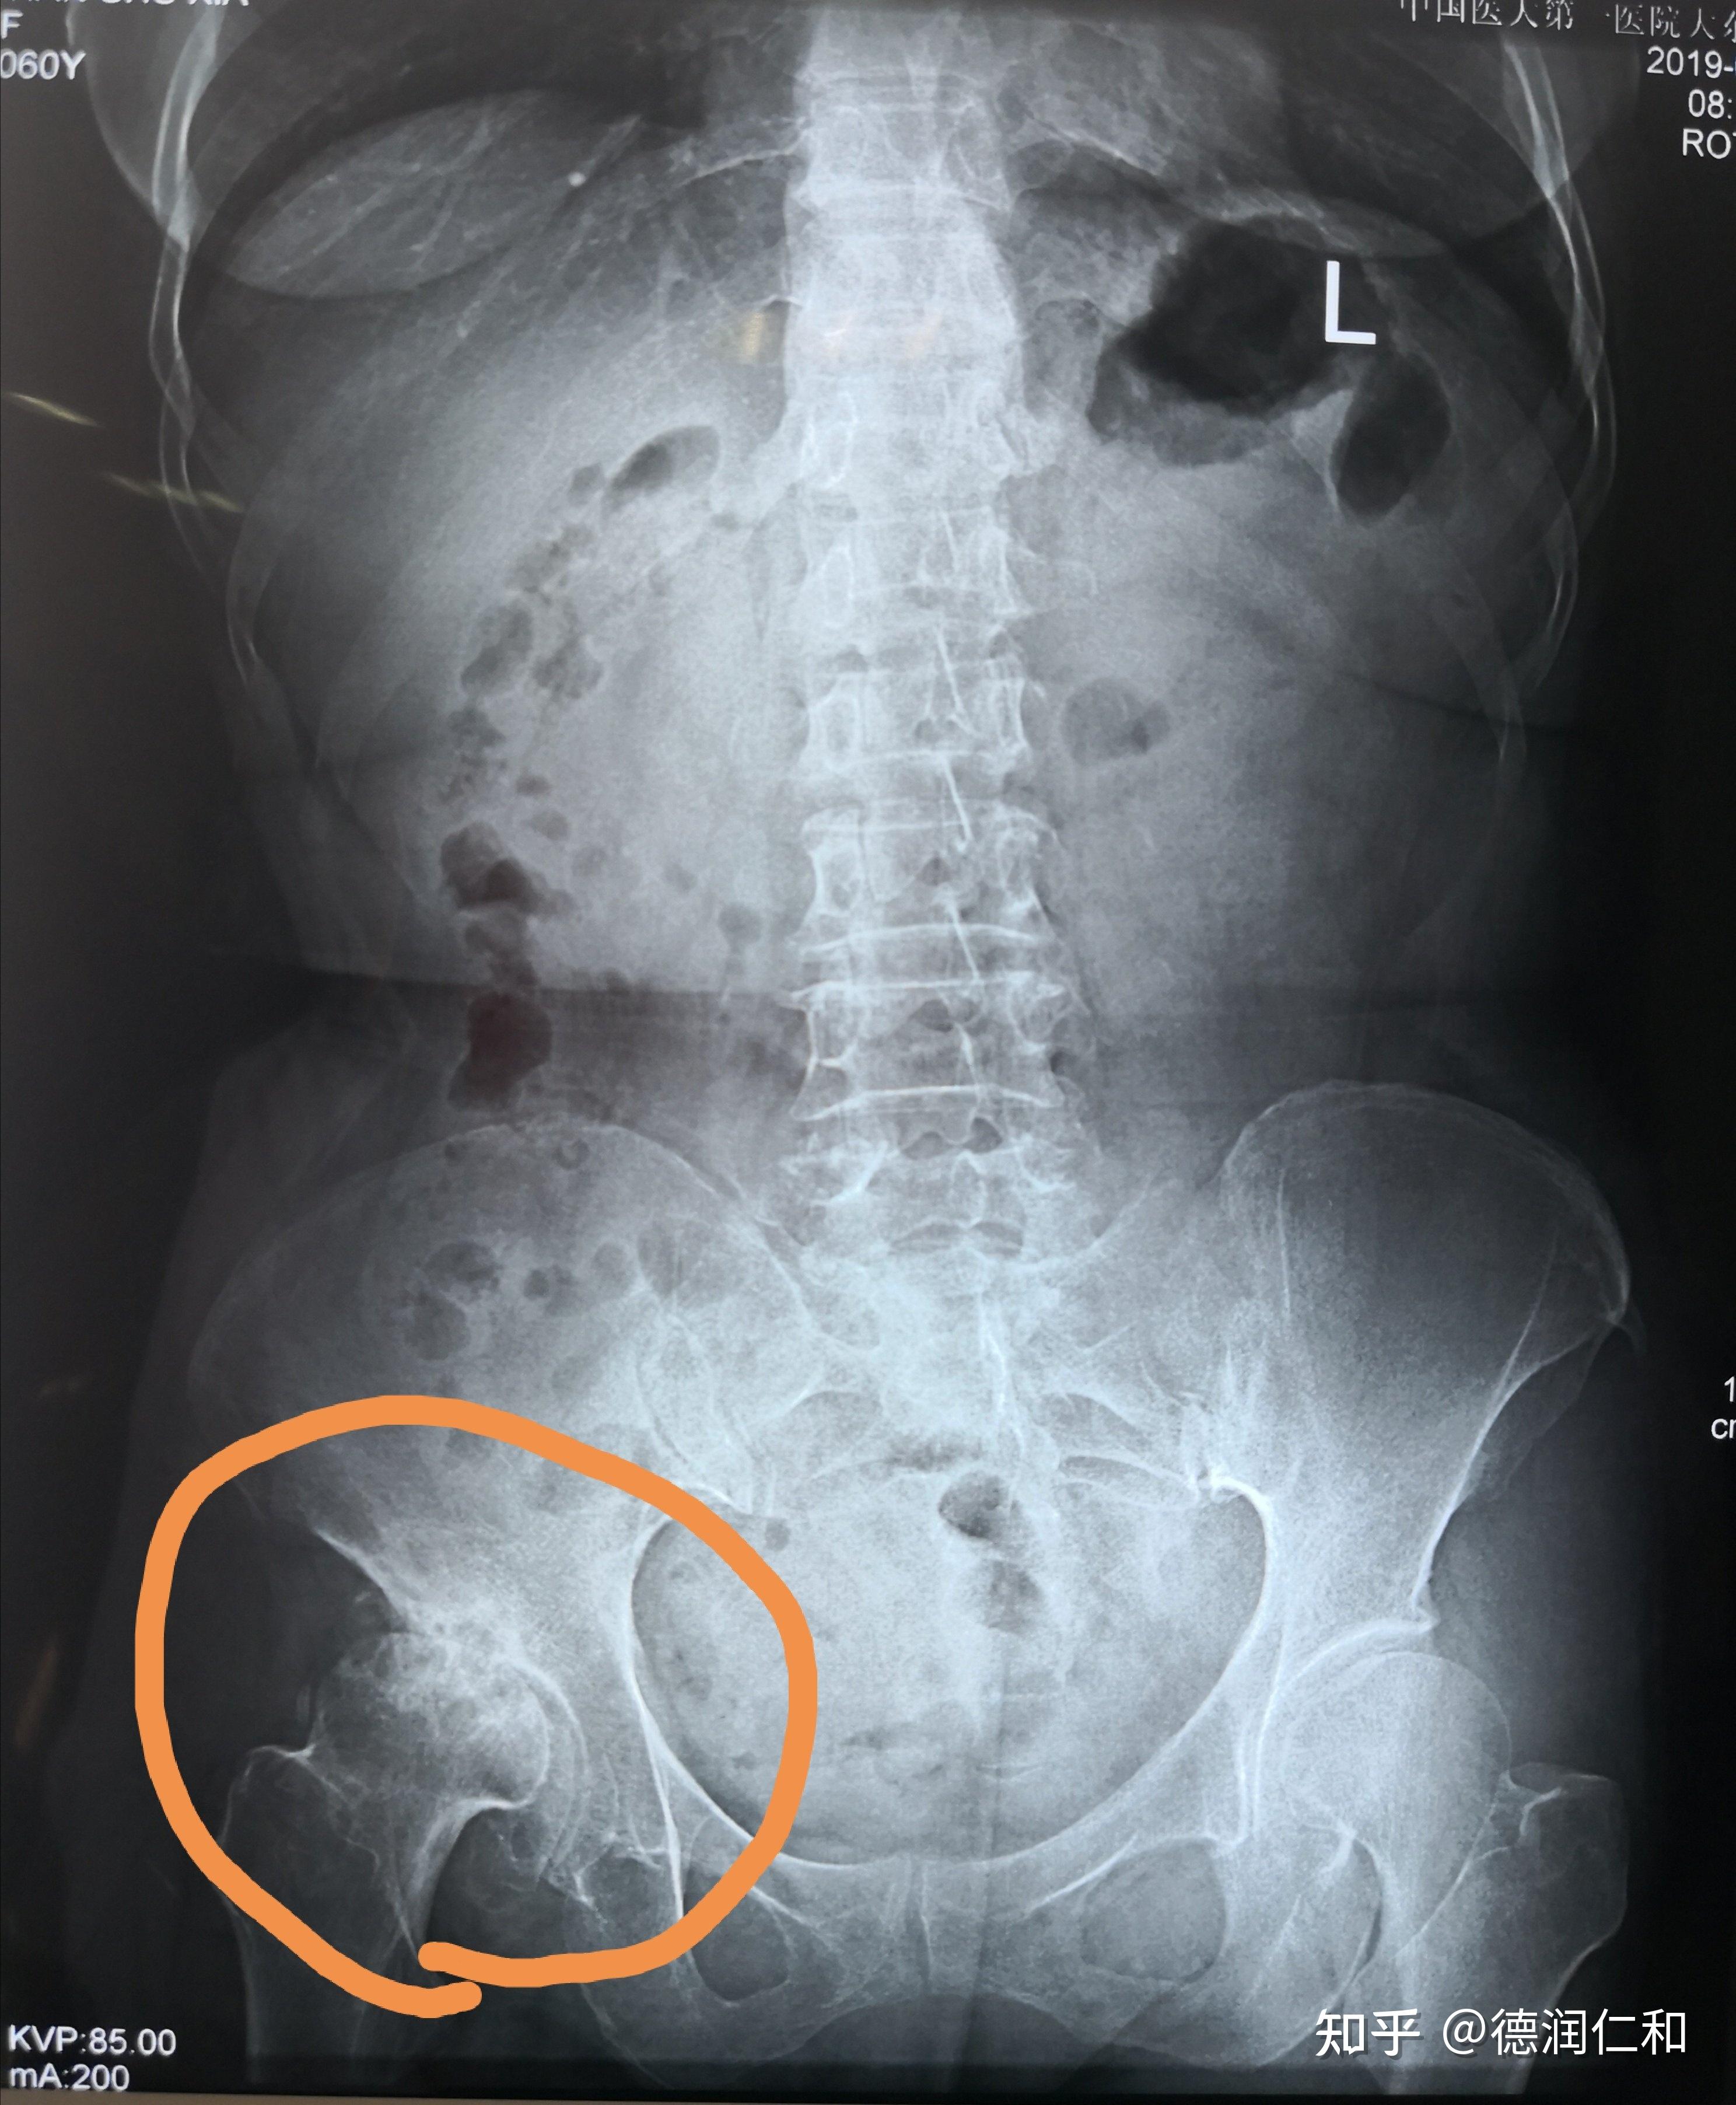

双侧股骨头坏死,也不要着急做关节置换

44岁,双侧酒精性股骨头坏死,先后两次髋关节置换手术,先是右侧,然而